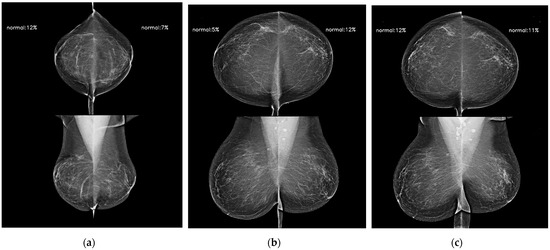

Artificial Intelligence-Powered Imaging Biomarker Based on Mammography for Breast Cancer Risk Prediction

by Eun Kyung Park, Hyeonsoo Lee, Minjeong Kim, Taesoo Kim, Junha Kim, Ki Hwan Kim, Thijs Kooi, Yoosoo Chang and Seungho Ryu

Diagnostics 2024, 14(12), 1212; https://doi.org/10.3390/diagnostics14121212 - 7 Jun 2024

The purposes of this study were to develop an artificial intelligence (AI) model for future breast cancer risk prediction based on mammographic images, investigate the feasibility of the AI model, and compare the AI model, clinical statistical risk models, and Mirai, a state [...] Read more.

The purposes of this study were to develop an artificial intelligence (AI) model for future breast cancer risk prediction based on mammographic images, investigate the feasibility of the AI model, and compare the AI model, clinical statistical risk models, and Mirai, a state of-the art deep learning algorithm based on screening mammograms for 1–5-year breast cancer risk prediction. We trained and developed a deep learning model using a total of 36,995 serial mammographic examinations from 21,438 women (cancer-enriched mammograms, 17.5%). To determine the feasibility of the AI prediction model, mammograms and detailed clinical information were collected. C-indices and area under the receiver operating characteristic curves (AUCs) for 1–5-year outcomes were obtained. We compared the AUCs of our AI prediction model, Mirai, and clinical statistical risk models, including the Tyrer–Cuzick (TC) model and Gail model, using DeLong’s test. A total of 16,894 mammograms were independently collected for external validation, of which 4002 were followed by a cancer diagnosis within 5 years. Our AI prediction model obtained a C-index of 0.76, with AUCs of 0.90, 0.84, 0.81, 0.78, and 0.81, to predict the 1–5-year risks. Our AI prediction model showed significantly higher AUCs than those of the TC model (AUC: 0.57; p < 0.001) and Gail model (AUC: 0.52; p < 0.001), and achieved similar performance to Mirai. The deep learning AI model using mammograms and AI-powered imaging biomarkers has substantial potential to advance accurate breast cancer risk prediction. Full article

Show Figures

Figure 1